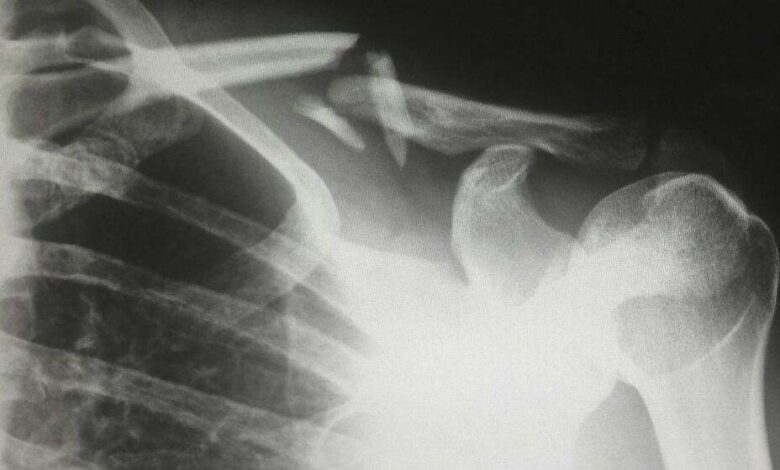

Eso sí, pese a que continúa siendo el elegido por las personas -sobre todo de avanzada edad- en la actualidad, los expertos han desvelado en los últimos meses otras vitaminas para proteger contra las fracturas y la osteoporosis, la enfermedad que debilita los huesos.

3. Vitamina CEs útil para la reconstrucción ósea y porque reduce el riesgo de fracturas de cadera. Se puede apreciar en cítricos, tomates…